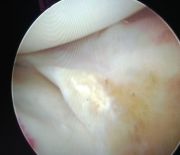

1. Popliteal extraskeletal chondroma of the right knee in a 38-year-old female.

Treatment: Surgical removal

I. Before the surgery , lateral x-ray of the knee shows the chondroma (red arrow) II. Post-surgery, lateral x-ray of the knee shows that the chondroma has been removed III. Post-surgery, the photo (posterior site of the knee) is showing the specific approach that has been used for the operation.